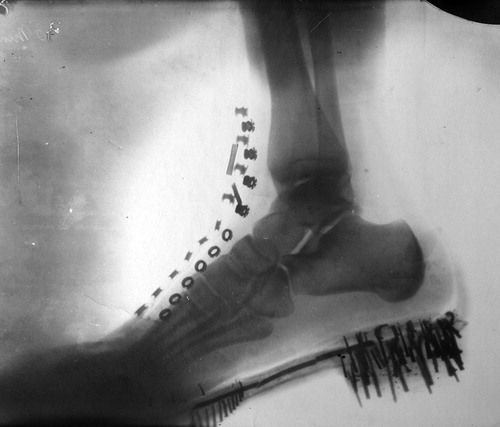

Desde su descubrimiento en 1895 por parte del profesor alemán Wilhelm Röntgen los rayos X han jugado un papel fundamental en las sociedades humanas. Son usados en campos tan distintos como el sanitario, la seguridad en el transporte e incluso la identificación de obras de arte. Su utilización está tan extendida que a veces deja imágenes tan curiosas como las recogidas en esta galería.